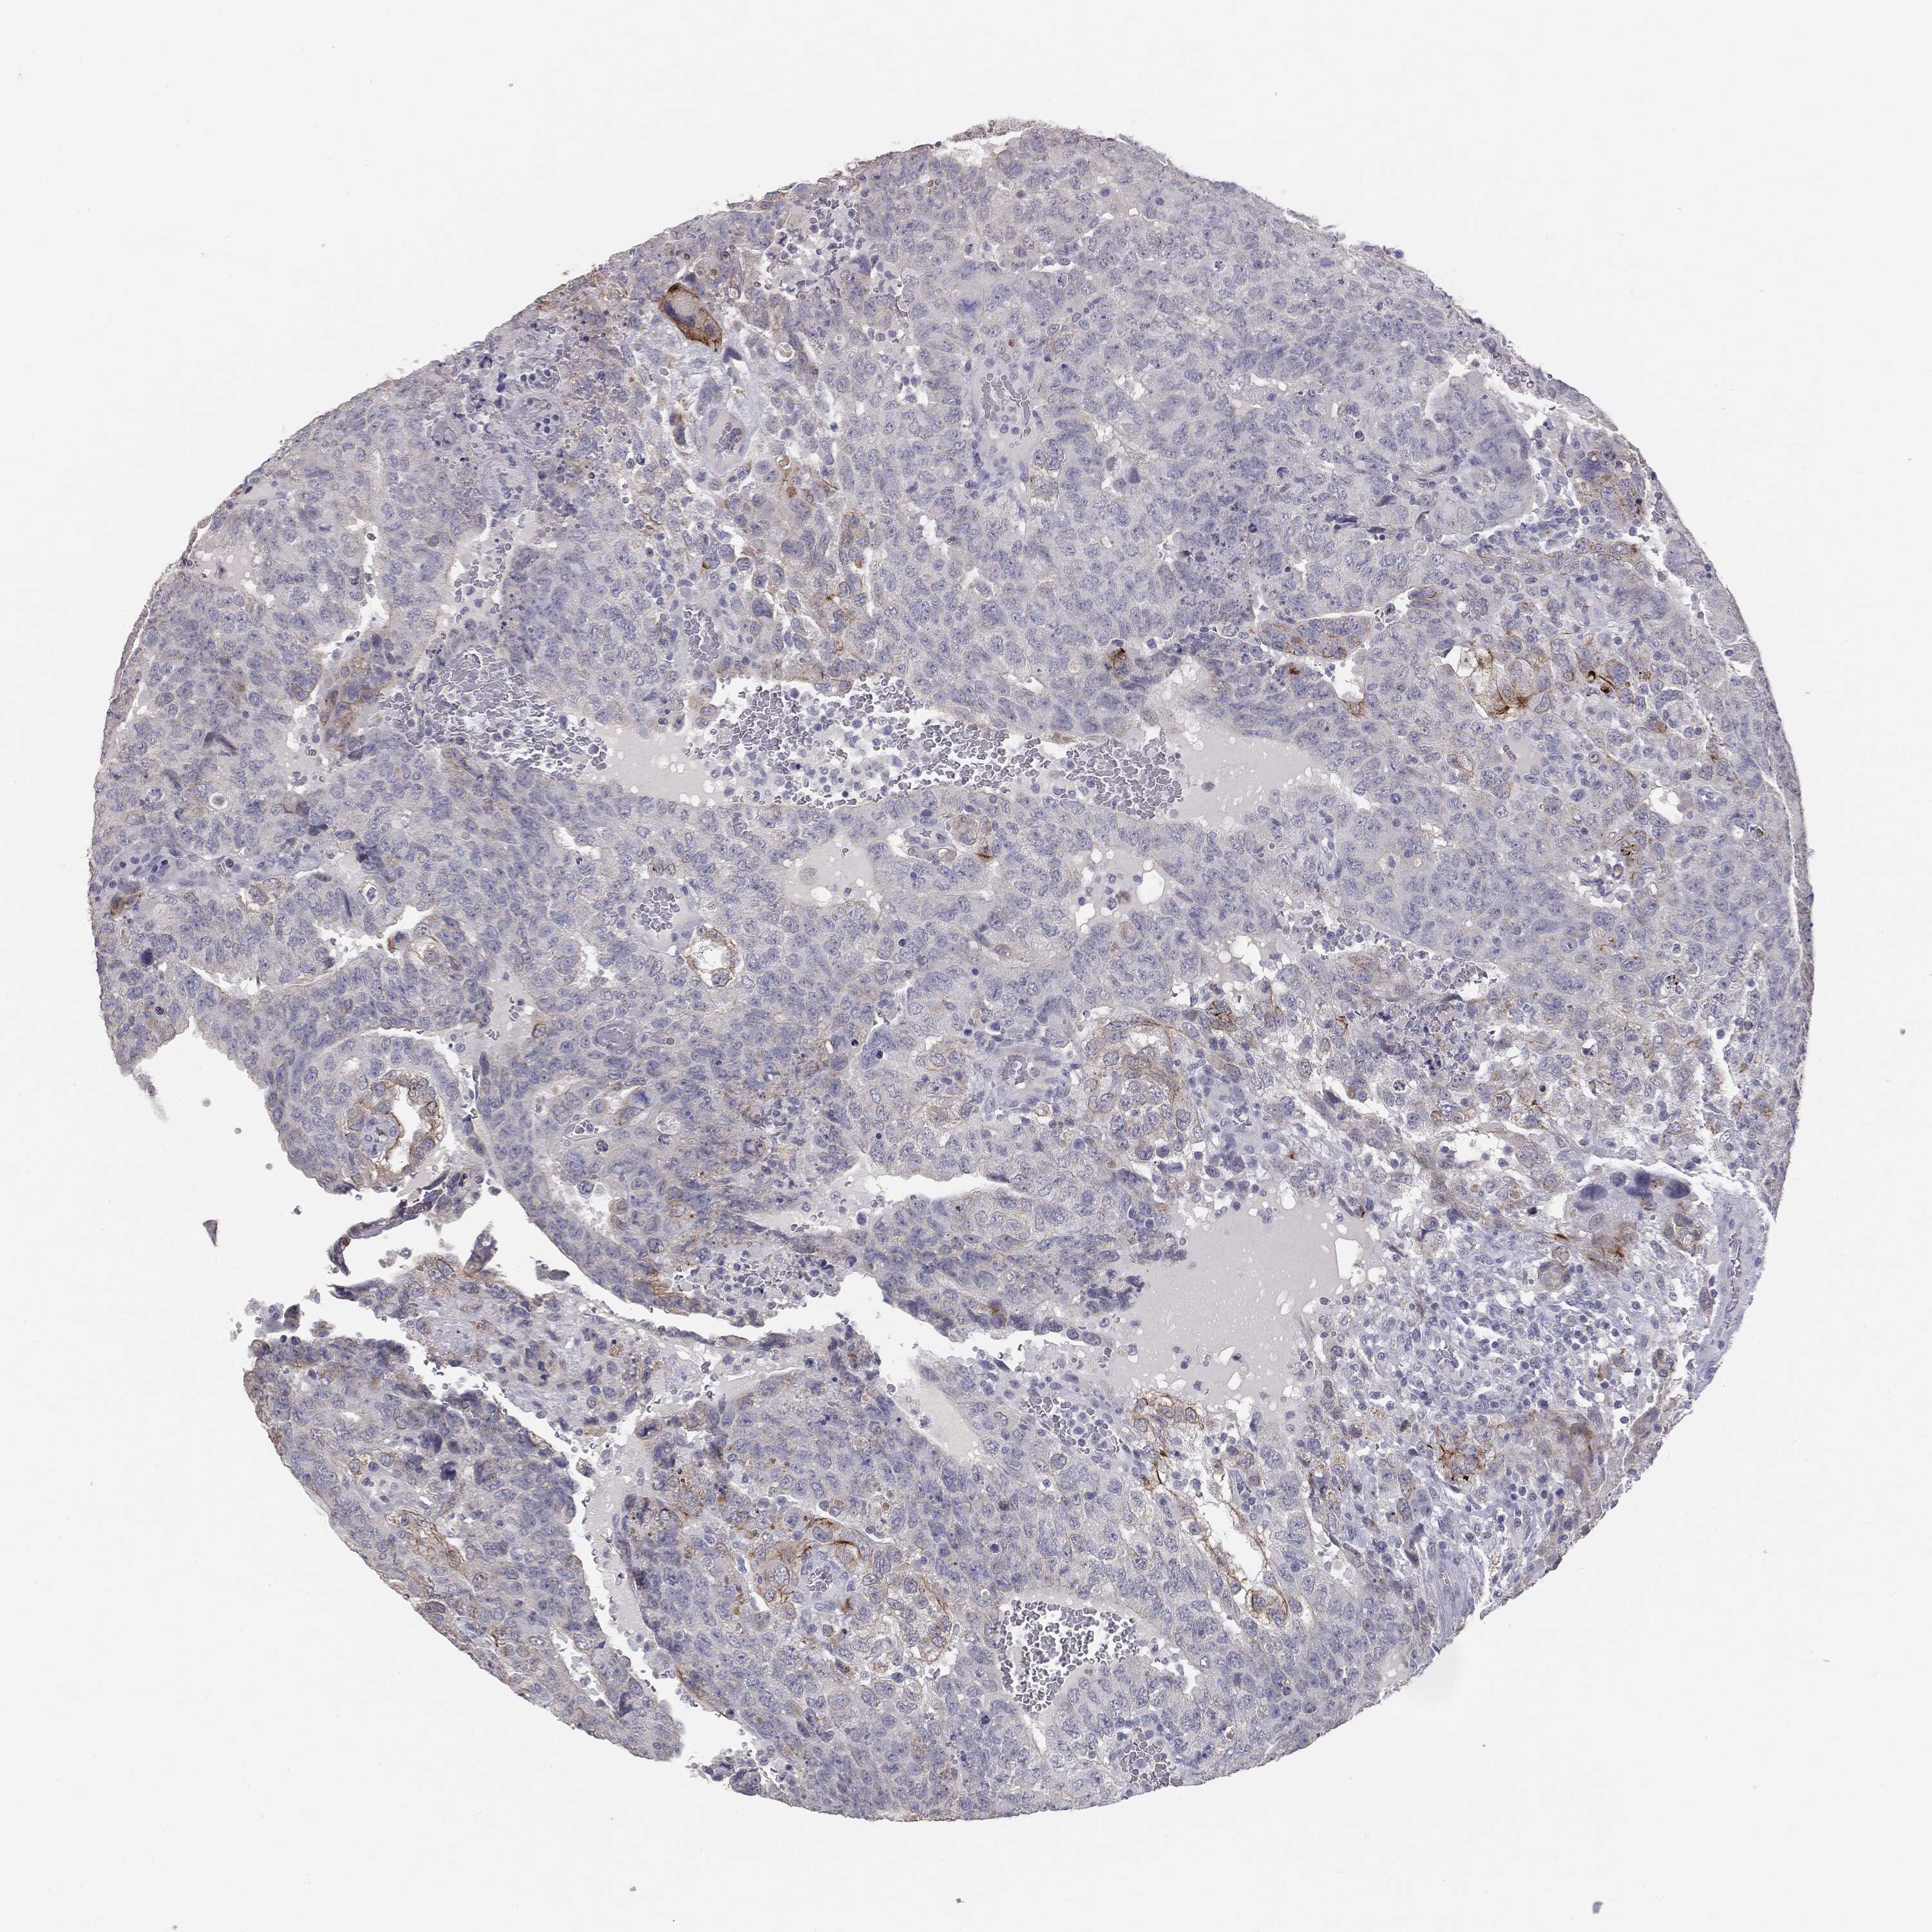

TESTIS CANCER - Protein expressioni

A mouse-over function shows sample information and annotation data. Click on an image to view it in a full screen mode. Samples can be filtered based on level of antibody staining by selecting one or several of the following categories: high, medium, low and not detected. The assay and annotation is described here.

Note that samples used for immunohistochemistry by the Human Protein Atlas do not correspond to samples in the TCGA dataset.

Antibody stainingi

Antibody staining in the annotated cell types in the current human tissue is reported as not detected, low, medium, or high, based on conventional immunohistochemistry profiling in selected tissues. This score is based on the combination of the staining intensity and fraction of stained cells.

Each image is clickable and will lead to virtual microscopy that enables deeper exploration of all samples and also displays staining intensity scores, fraction scores and subcellular localization as well as patient and tissue information for each sample.

HPA004179

HPA007235

HPA008855

CAB000036

CAB001986

CAB080102

CAB080103

Carcinoma, Embryonal, NOS

Seminoma, NOS

Teratoma, malignant, NOS

Urothelial carcinoma, High grade